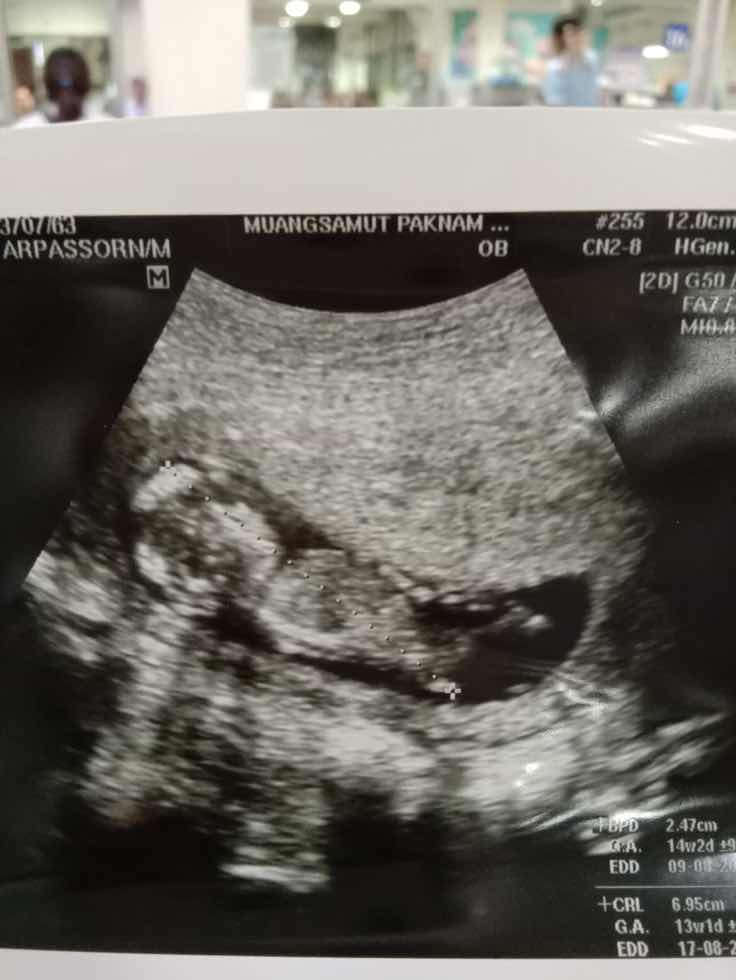

14w